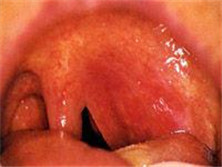

老先生三年前你得扁桃體癌,今天食管也有問題。這個病人患有扁桃體癌,現(xiàn)在又患上了食管腫瘤。當(dāng)天她被確診為扁桃體癌晚期和口腔癌晚期。但是一看您這個病史有扁桃體腫瘤,然后食管也有腫瘤,無一例外。...